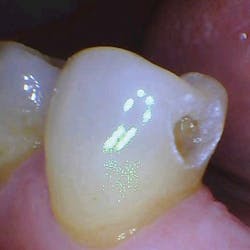

The removal of dental hard tissue is accomplished by what is known as thermomechanical photon-induced water-mediated ablation, which is a process in which the micro-explosive force of photons on water droplets results in the selective removal of carious dentin (figures 2a–2d). The laser energy seeks out tissue with higher water content, such as a carious lesion, and evaporates it without contact, vibration, or the introduction of microfractures, leaving the surrounding healthy enamel and dentin intact.

Figures 2a–2d: A Class II posterior cavity preparation